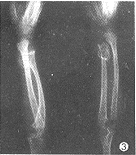

例3 女,6岁。无诱因出现右腕部肿块渐增大而就诊。查体见右腕部肿块约2.5cm×2.5cm大小,质硬,无压痛。X线片示:右尺骨发育短小,远端骨性突起,前方软组织受推移,尺桡骨弯曲,下尺桡关节半脱位,腕骨发育迟缓。右肱骨上段及左肩胛骨下角均有骨性突起。X线诊断:多发性骨软骨瘤继发假性Madelung畸形(图3)。手术切除右腕部肿块,病理报告:骨软骨瘤。

图1 左桡骨远端骨软骨瘤,桡骨弯曲,左尺骨短小,远端变形,下尺桡关节脱位,腕骨排列失常,形成以月骨为中心锥形排列图2 右桡骨中段骨软骨瘤,其远端骨骺内侧发育较小,下尺桡关节半脱位,腕骨角变小,形成以月骨为中心锥形排列 图3 右尺骨骨软骨瘤,尺桡骨弯曲,尺骨发育短小,下尺桡关节脱位,腕骨发育迟缓